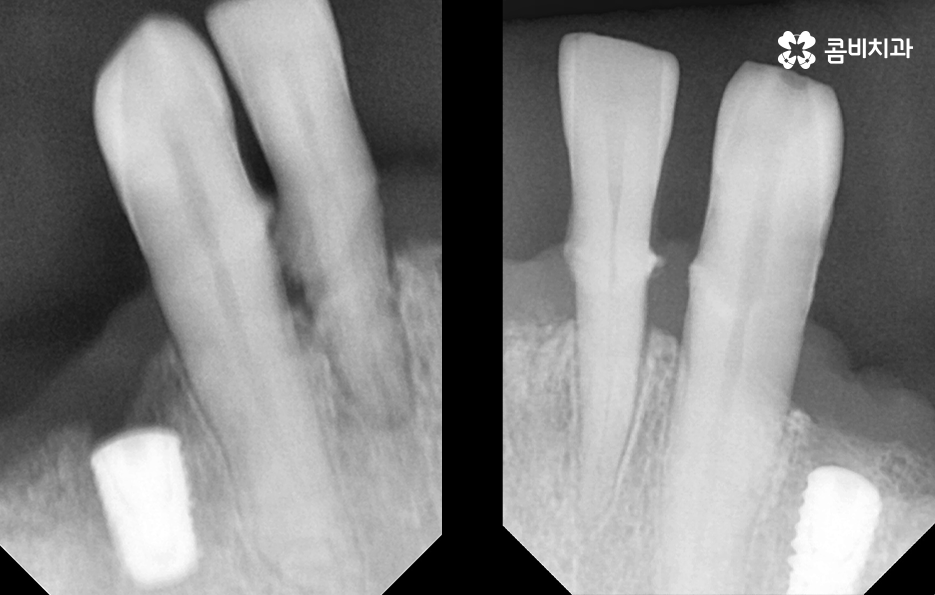

하지만 노년층의 환자분들의 경우 경제적인 부분이 부담스럽거나 치아를 잃은 개수만큼 임플란트를 식립하고 싶어도 잇몸 상태가 너무 좋지 않은 경우에는 임플란트 식립을 해야 하는 개수를 줄이고 치아의 머리부분을 연결하는 브릿지 형태로 임플란트 시술을 진행하는 경우가 있는데요

전체임플란트 해야 하는 상황에서 가장 권장하는 방법은 치아를 잃은 개수만큼 임플란트를 식립하는 방법이 되겠지만 그다음으로 잇몸 상태나 경제적 상황 등을 고려할 때 선택할 수 있는 방법 중 하나는 임플란트 브릿지를 활용한 치료 방법이라 할 수 있어요

잇몸 상태가 너무 안 좋은 경우에도 치아를 상실한 상태로 그대로 두면 심미적으로나 치아의 기능적으로나 안 좋기 때문에 잇몸 뼈의 상태가 좋은 부분 위주로 골라서 임플란트를 식립하고 브릿지의 형태를 차선책으로 볼 수 있어요